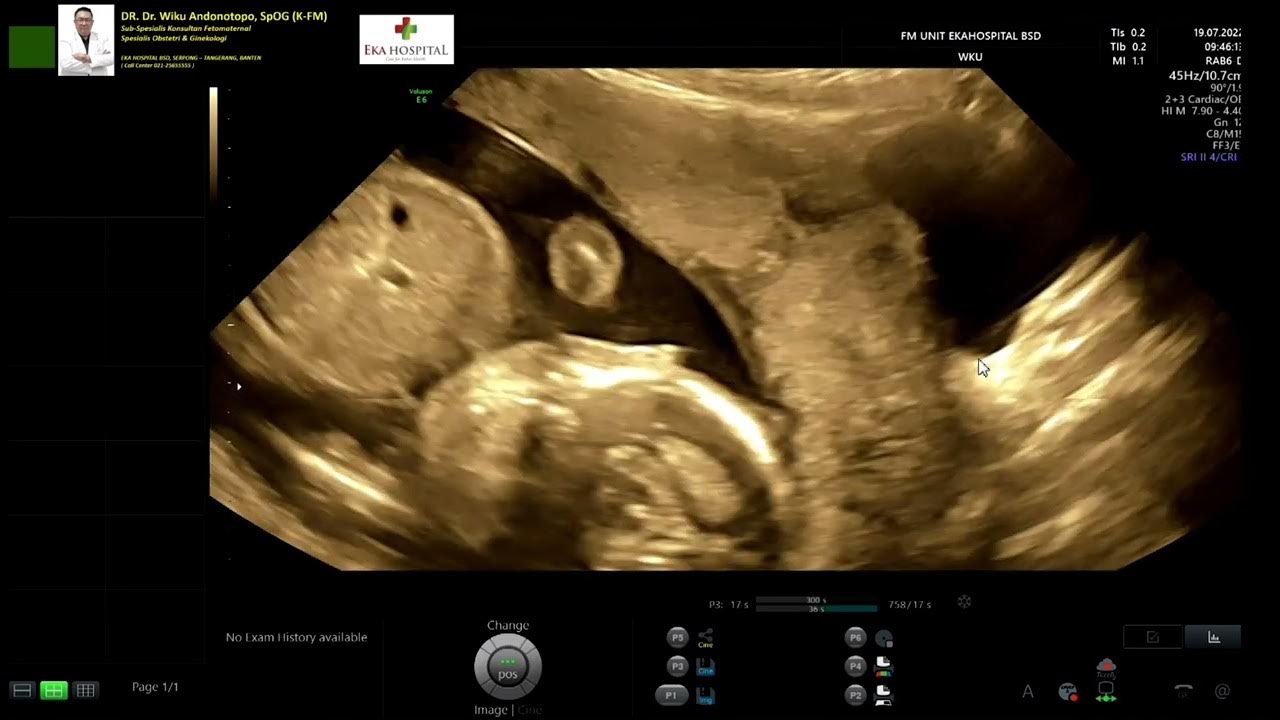

Complete Placenta Previa Ultrasound Case 91 YouTube from www.youtube.com

Complete Placenta Previa Ultrasound Case 91 YouTube